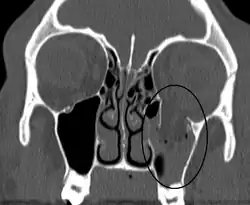

| An orbital blowout fracture of the floor of the left orbit. | |

Thin cut (2-3mm) CT scan with axial and coronal view is the optimal study of choice for orbital fractures.[16][17]

Plain radiographs, on the other hand, do not have the sensitively capture blowout fractures.[18] On Water's view radiograph, polypoid mass can be observed hanging from the floor into the maxillary antrum, classically known as teardrop sign, as it usually is in shape of a teardrop. This polypoid mass consists of herniated orbital contents, periorbital fat and inferior rectus muscle. The affected sinus is partially opacified on radiograph. Air-fluid level in maxillary sinus may sometimes be seen due to presence of blood. Lucency in orbits (on a radiograph) usually indicate orbital emphysema.[4]